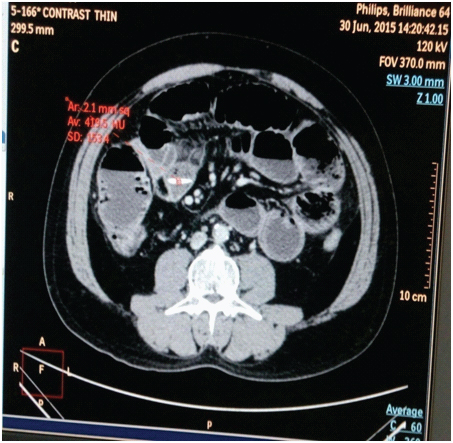

Computed tomography (CT) of the abdomen demonstrated multiple loops of dilated, gas and fluid-filled small bowel measuring up to 4.5 cm with a 3.9×0.5 cm high attenuation linear structure lying transversely in the lumen of the distal small bowel, 30-40 cm from the ileo-caecal valve [Table/Fig-2]. There was no free intraperitoneal gas. After taking informed consent, patient underwent laparotomy, intraoperative finding revealed dialated small bowel loop with trasition zone in distal ileum, where on palpation a long, thin bone fragment was lying transversely, along with two other small pieces just proximal to it lying longitudenly. Bone fragment removed through enterotomy [Table/Fig-3,4]. Bowel decompression done, then enterotomy wound closed. Postoperatively on enquiry, he admits that he had consumed chicken meat 36 hours prior to presentation. The postoperative period was uneventful and patient was discharged on the 7th postoperative day.

CT scan showing linear dense radio-opaque object lying transversely in ileum.